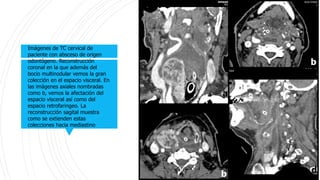

Imágenes de TC cervical de

paciente con absceso de origen

odontógeno. Reconstrucción

coronal en la que además del

bocio multinodular vemos la gran

colección en el espacio visceral. En

las imágenes axiales nombradas

como b, vemos la afectación del

espacio visceral así como del

espacio retrofaringeo. La

reconstrucción sagital muestra

como se extienden estas

colecciones hacia mediastino